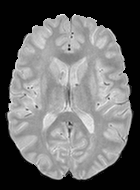

We observed that memberships predicted with an FC layer result in more false positives compared to a fully convolutional network. An example is shown in Fig. 2, where lesion memberships are generated from MPRAGE and FLAIR using the proposed model of convolutional pathways and a comparable model where the last convolutional pathway after concatenation (see Fig. 1) is replaced with a FC layer predicting voxel-wise memberships. The membership image generated with an FC layer, although being close to inside the lesions, has high values () in the left and right frontal cortex where the FLAIR image shows some artifacts. However, the membership obtained with the proposed method shows relatively low values near the frontal cortex.

With FC layer, voxel-wise predictions are performed for each voxel on a new image. Therefore the prediction time for the whole image comprising millions of voxels can take some time even on a GPU, as mentioned in Wachinger et al. (2017). In contrast, with fully convolutional prediction, lesion membership estimation of a mm3 MR volume of size takes only a couple of seconds. Note that although patches are used for training, the final trained model contains only convolution filters and does not depend in any way on the input patch size. Therefore during testing, the lesion membership of a whole 2D slice, irrespective of the slice size, is predicted at a time by applying convolutions on the whole slice. Without an FC layer, the images need not be decomposed into sub-regions, e.g., Kamnitsas et al. (2017). Consequently, there is no need to employ membership smoothing between sub-regions. In addition, since the training memberships, generated by Gaussian blurring of hard segmentations, are smooth, the resultant predicted memberships are also smooth (Fig. 2 last column).